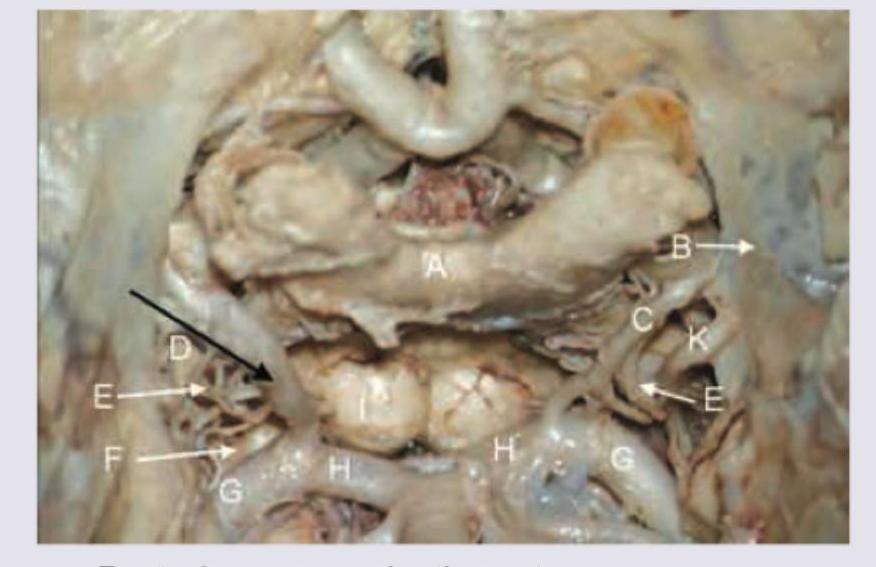

Identify the artery labelled with black arrow in the given diagram.

Explanation: ***Superior cerebellar artery*** - The superior cerebellar artery (SCA) typically originates from the **distal basilar artery**, just before its bifurcation into the posterior cerebral arteries. - In the provided image, the artery indicated by the black arrow is seen branching off the **basilar artery** (labeled H) and curving over the superior aspect of the cerebellum/brainstem, consistent with the SCA. *Posterior communicating artery* - The posterior communicating artery (PCOM) connects the **internal carotid artery** to the **posterior cerebral artery**. - This artery is part of the **Circle of Willis** and is located more anteriorly in relation to the basilar artery and cerebellum, and is not shown by the arrow. *Anterior inferior cerebellar artery* - The anterior inferior cerebellar artery (AICA) originates from the **lower third of the basilar artery** and supplies the anterior and inferior aspects of the cerebellum. - Its position is typically more caudal than the artery indicated by the black arrow, which is seen at a higher level with respect to the brainstem. *Basilar artery* - The basilar artery (labeled H) is a large, midline artery formed by the union of the two **vertebral arteries** and runs along the ventral surface of the pons. - The black arrow points to a vessel branching off the main basilar artery, not the basilar artery itself.